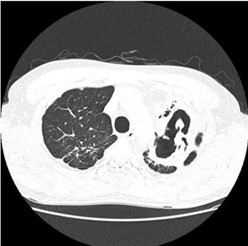

CT scan of peritoneal tuberculosis, with thickened omentum and peritoneal surface

Extrapulmonary tuberculosis (EPTB) is a form of tuberculosis that affects organs or tissues outside of the lungs. It can affect any part of the body, including the skin, lymph nodes, abdomen, bones, joints, genitourinary tract, meninges, and heart. EPTB is less common than pulmonary TB, accounting for approximately 20% of all TB cases.

It is often more challenging to diagnose than pulmonary TB because the symptoms may not be as obvious. Symptoms can vary depending on the location and severity of the infection but may include fever, night sweats, weight loss, and swelling or pain in the affected area.